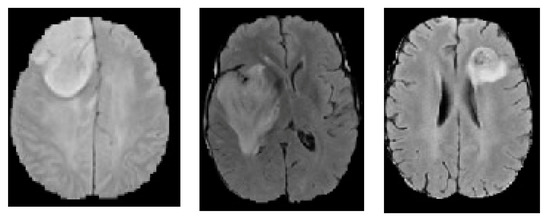

- Groza, V.; Tuchinov, B.; Pavlovskiy, E.; Amelina, E.; Amelin, M.; Golushko, S.; Letyagin, A. Data preprocessing via multi-sequences MRI mixture to improve brain tumor segmentation. In Proceedings of the International Conference on Bioinformatics and Biomedical Engineering, Granada, Spain, 6–8 May 2020; Springer International Publishing: New York, NY, USA, 2020; pp. 695–704. [Google Scholar]